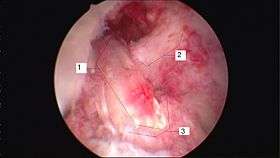

Arthroscopic anterior cruciate ligament (ACL) reconstruction (right knee). The tendon of the semitendinosus muscle was prelevated, folded and used as an autograft (1). It appears through the remnant of the injured original ACL (3). The autograft then courses upwardly and backwardly in front of the posterior cruciate ligament (2). | |